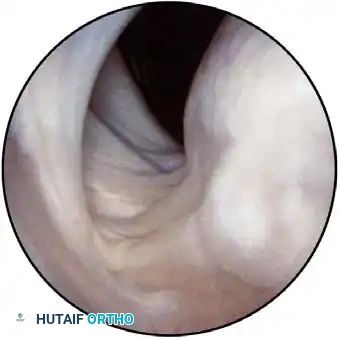

Routine diagnostic arthroscopy is performed using a 4-mm, 30-degree oblique arthroscope. This angle allows for comprehensive visualization of the entire joint through rotation of the lens and manipulation of the arm. In complex instability cases, switching to a 70-degree arthroscope dramatically improves visualization of the anterior glenoid neck and the inferior glenohumeral ligament, which is critical during arthroscopic capsulorrhaphy.

Once diagnostic evaluation is complete and hemostasis is secured, the therapeutic phase commences. Whether performing a SLAP repair, a Bankart stabilization, or a rotator cuff repair, the principles of tissue mobilization, anatomical footprint restoration, and secure biomechanical fixation remain paramount.

Modern arthroscopy relies heavily on suture anchors (biocomposite or all-suture constructs) and advanced arthroscopic knot-tying or knotless techniques. The ability to pass sutures through retracted, fibrotic tissue and secure them under appropriate tension without strangulating the microvascular supply is the hallmark of a master arthroscopist.